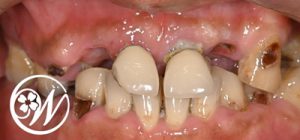

初診時

「噛めない」「見た目が悪い」というお悩みで来院されました。

検査の結果、上顎は咬み合わせが大きく崩れた“咬合崩壊”の状態で、機能面・審美面ともに回復が必要な状態でした。

そのため、フルアーチでのインプラント治療が適応と判断しました。

また下顎にも奥歯の欠損がみられ、こちらもインプラントによる補綴治療を行う方針としました。